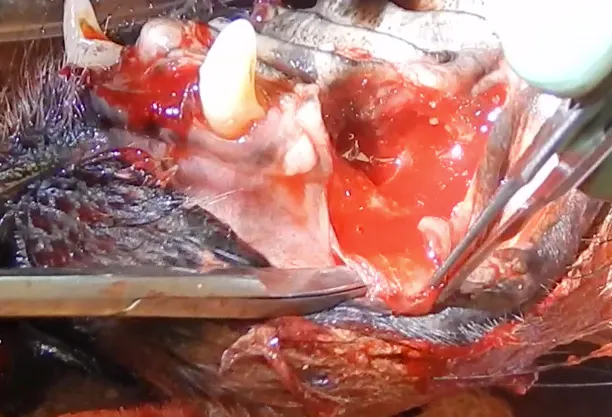

Most tooth extractions and many periodontal treatments require elevation of mucogingival flaps for appropriate removal of buccal alveolar bone. Gingival flap dehiscence (Figure 1) is the most common complication of dental extractions and often occurs with other types of maxillofacial surgery.3 Dehiscence is more common when gingival tissue is damaged by aggressive tissue handling during surgery or when a gingival flap is closed under tension.

(A) A dog with a large area of dehiscence associated with left maxillary canine tooth extraction; a large oronasal fistula is visible with yellow foreign material present in the nasal cavity (arrow). (B) A dog with a small area of dehiscence associated with left maxillary canine tooth extraction; an oronasal fistula is visible in the center of the extraction site closure (arrow).